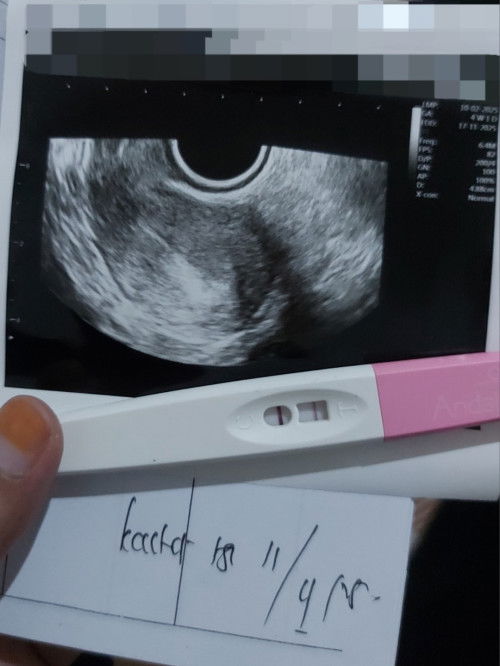

HPHT 10 Feb Tadi pagi tespek garis 2 jelas dan malam ny langsung ke SpOG

MasyaAllah, dokter yg ngejelasin baik bgt. Walaupun masih terlalu dini buat USG, kta dokter nya ini udh positif hamil. Sudah penebalan dinding rahim dan kemungkinan ada kantung ny cm masih kecil banget hehee. Di kasi tau buat USG bulan depan, insyaAllah udh keliatan nnti. Doain ya bunda", semoga bulan depan hasil nya bagus dan dedek nya ada di posisi yg sesuai. Buat yg belum garis 2 atau masih samar, semangat yaa. Semoga lekas di beri kabar baik, aamiinđ #Sharingdong_Bund #firstmom #sharing